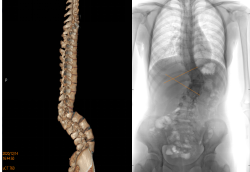

患者15岁,正是花季的年龄,其腰渐渐地疼痛和变形,到医院就诊,诊断为先天性半椎体畸形,让她陷入了恐慌和绝望中。

▲ 术前Cobb 角侧凸57°后凸82°

正当以为她的青春与学业无法为继的时候,脊柱外科米明珊专家团队让她重新燃起了希望之光。

在完善检查准备工作后,对她实施了后路一期半椎切除侧后凸畸形矫形重建手术。切除半椎体后,为了减轻脊髓的张力减少皱褶产生的后遗症。创新性地应用了椎间融合器来平衡缺损区加速病变节段的融合防止畸形复发。

▲ 术后Cobb角侧凸9°后凸10°,矫正满意

术后畸形消失,在加速康复小组治疗后,患者仅用3周就恢复了正常行走,如期佩戴支具,回到了校园继续努力学习生活。